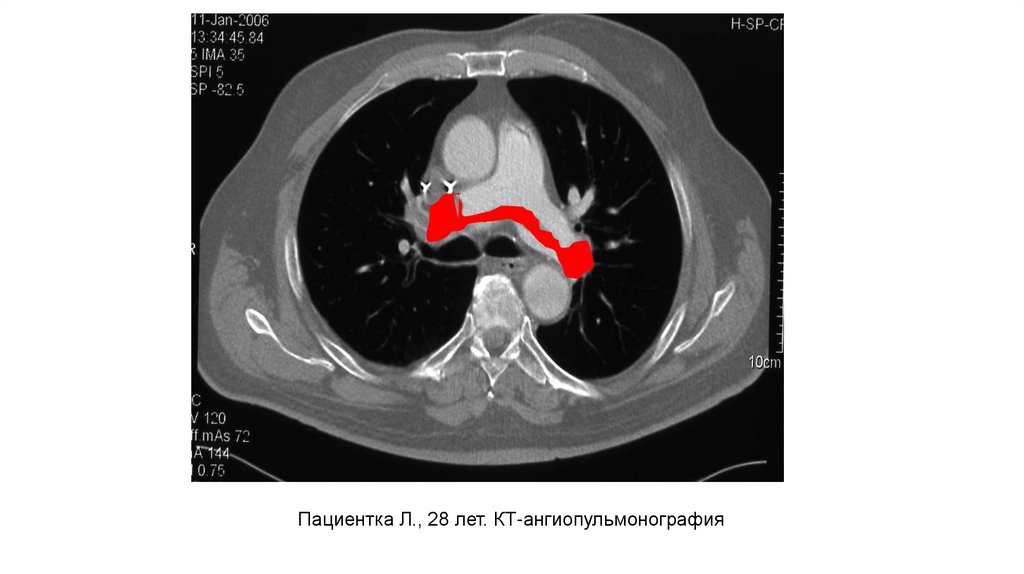

Пациентка Л., 28 лет. КТ-ангиопульмонография

4.